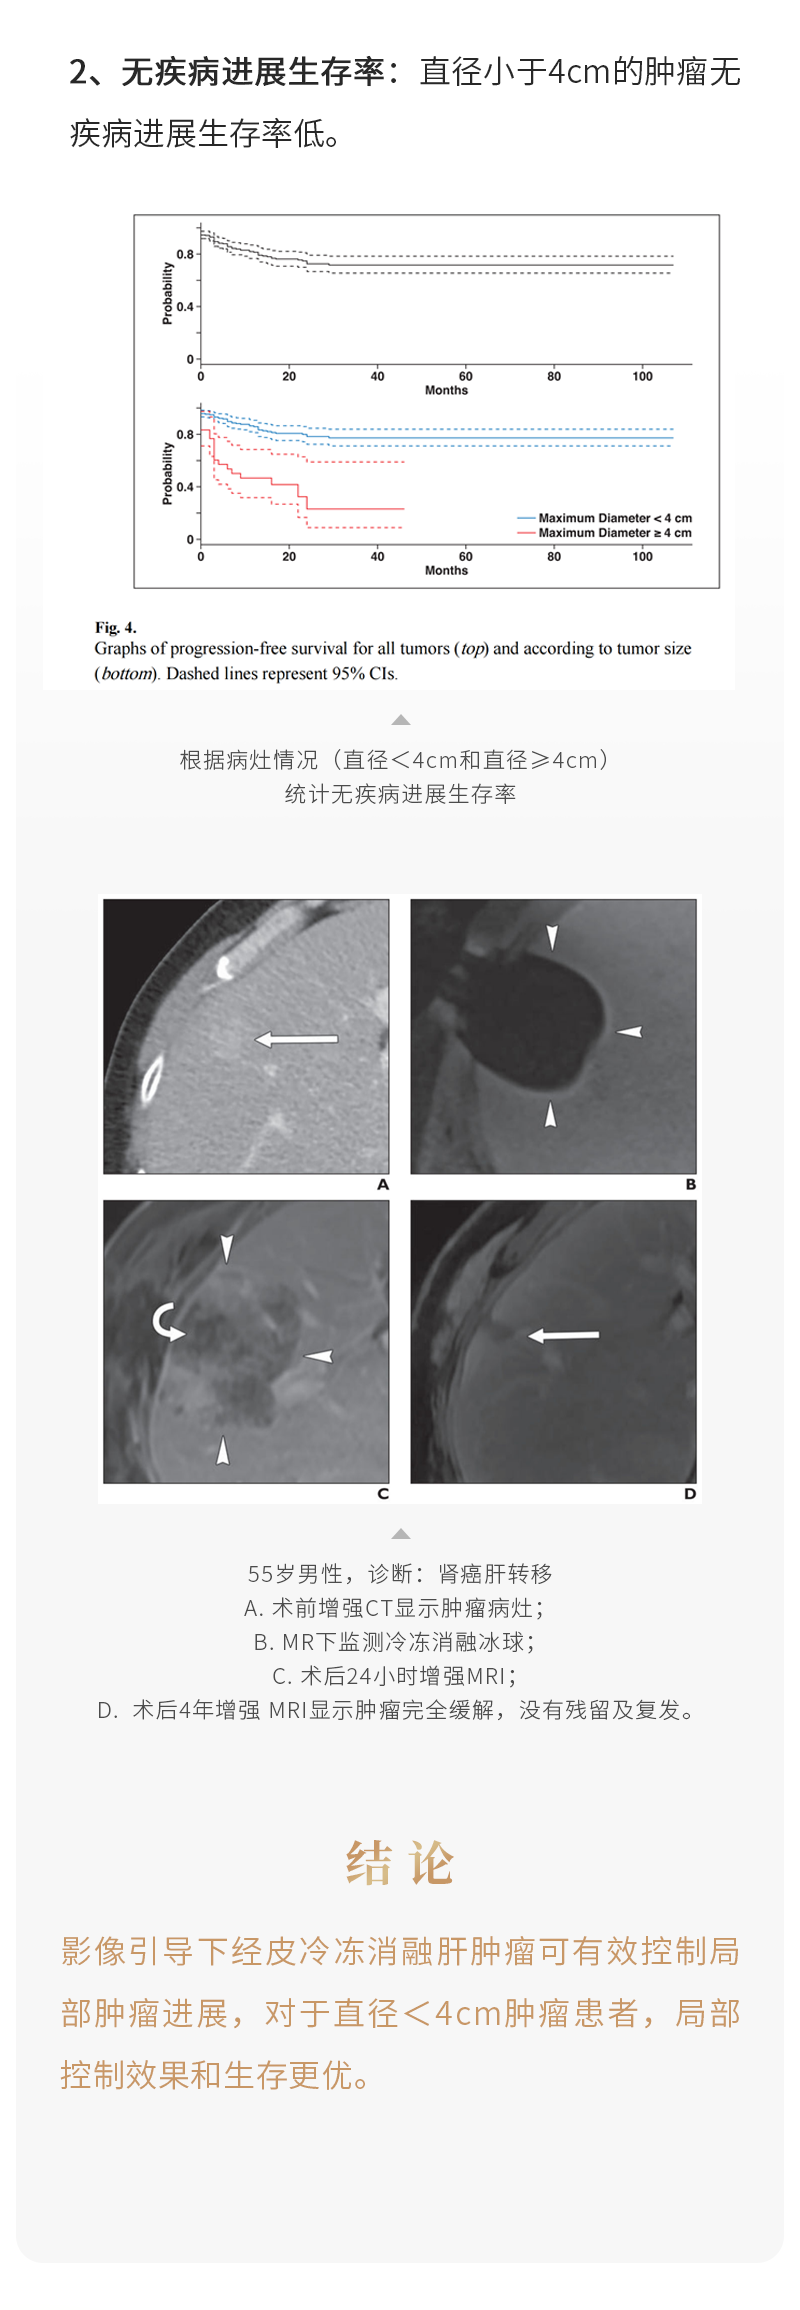

冷凍消融治療肝轉(zhuǎn)移瘤安全有效——【海杰亞科研資訊】第236期